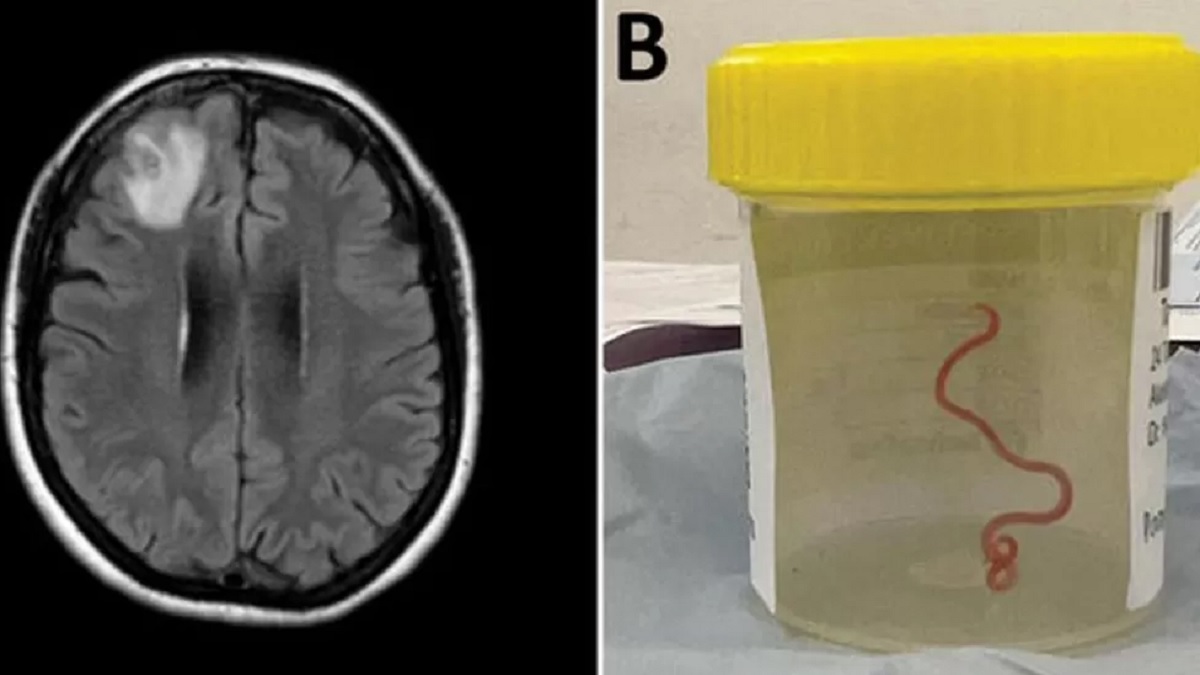

প্রথমবারের মতো জীবন্ত কৃমির সন্ধান মিললো মানুষের মস্তিষ্কে। অস্ট্রেলিয়ার ৬৪ বছর বয়সী এক নারীর মস্তিষ্কে অস্ত্রোপচারের পর বেরিয়ে এলো ৮ সেন্টিমিটারে একটি গোলকৃমি। খবর বিবিসি ও আল জাজিরার।

ক্যানবেরা হাসপাতালের চিকিৎসক ও অস্ট্রেলিয়ান ন্যাশনাল ইউনিভার্সিটির বিজ্ঞানীদের যৌথ গবেষণায় জানা যায়, কৃমিটির বৈজ্ঞানিক নাম ওফিডাসকারিস রবার্টসি। সাধারণত অজগর সাপের মধ্যে পাওয়া যায় এই কৃমি।

ভুলে যাওয়ার সমস্যা নিয়ে ২০২১ সালের জানুয়ারিতে হাসপাতালে ভর্তি হন ওই নারী। পরে পরীক্ষা নিরীক্ষার পর সংক্রমণজনিত কারণে তার মস্তিষ্কে অস্ত্রোপচারের সিদ্ধান্ত নেন চিকিৎসকরা। ২০২২ সালের জুনে অস্ত্রোপচার করা হলে আশ্চর্যজনকভাবে পরজীবিটি পাওয়া যায়।

কৃমিটি এখনও জীবিত ও নড়াচড়াও করছে। গবেষকরা জানিয়েছেন, ওই নারী যে এলাকায় বাস করতেন তার আশপাশে অজগরের আবাস ছিল। সেখান থেকে সংগ্রহ করা এক ধরনের ঘাস রান্নায় ব্যবহার করতেন তিনি। বিশেষজ্ঞদের ধারণা, ওই ঘাসের মাধ্যমেই তার শরীরে কৃমি প্রবেশ করেছে।